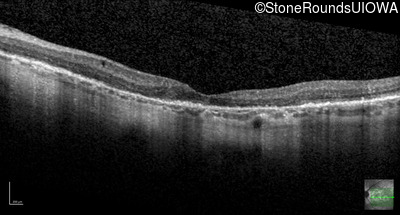

Optical Coherence Tomography - Left - 20/25 +3

Exemplar / OCT Stack

OCT Stack